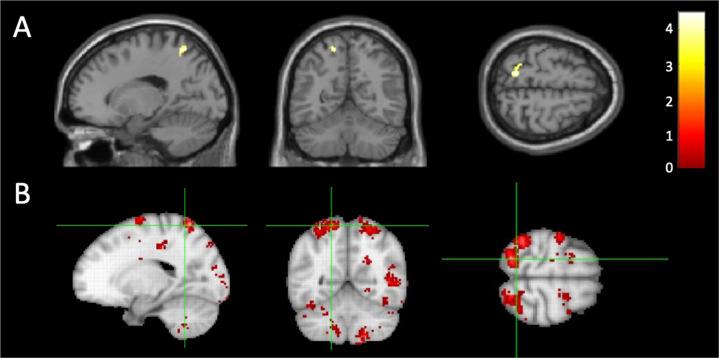

Child maltreatment dysregulates the brain's oxytocinergic system, resulting in dysfunctional attachment patterns. However, how the oxytocinergic system in children who are maltreated (CM) is epigenetically affected remains unknown. We assessed differences in salivary DNA methylation of the gene encoding oxytocin (OXT) between CM (n = 24) and non-CM (n = 31), alongside its impact on brain structures and functions using multi-modal brain imaging (voxel-based morphometry, diffusion tensor imaging, and task and resting-state functional magnetic resonance imaging). We found that CM showed higher promoter methylation than non-CM, and nine CpG sites were observed to be correlated with each other and grouped into one index (OXTmi). OXTmi was significantly negatively correlated with gray matter volume (GMV) in the left superior parietal lobule (SPL), and with right putamen activation during a rewarding task, but not with white matter structures. Using a random forest regression model, we investigated the sensitive period and type of maltreatment that contributed the most to OXTmi in CM, revealing that they were 5-8 years of age and physical abuse (PA), respectively. However, the presence of PA (PA+) was meant to reflect more severe cases, such as prolonged exposure to multiple types of abuse, than the absence of PA. PA+ was associated with significantly greater functional connectivity between the right putamen set as the seed and the left SPL and the left cerebellum exterior. The results suggest that OXT promoter hypermethylation may lead to the atypical development of reward and visual association structures and functions, thereby potentially worsening clinical aspects raised by traumatic experiences.

儿童虐待会扰乱大脑的催产素系统,导致依恋模式功能失调。然而,虐待儿童(CM)的催产素系统如何受到表观遗传影响尚不清楚。我们评估了 CM(n=24)和非-CM(n=31)之间编码催产素(OXT)的基因唾液 DNA 甲基化的差异,以及使用多模态脑成像(体素基形态计量学、弥散张量成像和任务和静息状态功能磁共振成像)对大脑结构和功能的影响。我们发现 CM 的启动子甲基化程度高于非-CM,并且观察到 9 个 CpG 位点相互关联并分为一个指数(OXTmi)。OXTmi 与左顶叶上回(SPL)的灰质体积(GMV)呈显著负相关,与奖励任务期间右壳核的激活呈负相关,但与白质结构无关。使用随机森林回归模型,我们研究了对 CM 中 OXTmi 贡献最大的敏感时期和虐待类型,结果表明是 5-8 岁和身体虐待(PA)。然而,PA(PA+)的存在意味着比没有 PA 更严重的情况,例如长时间暴露于多种类型的虐待。PA+与右壳核作为种子与左 SPL 和左小脑外部之间的功能连接显著增加有关。结果表明,OXT 启动子超甲基化可能导致奖励和视觉联想结构和功能的非典型发育,从而可能使创伤经历引起的临床方面恶化。